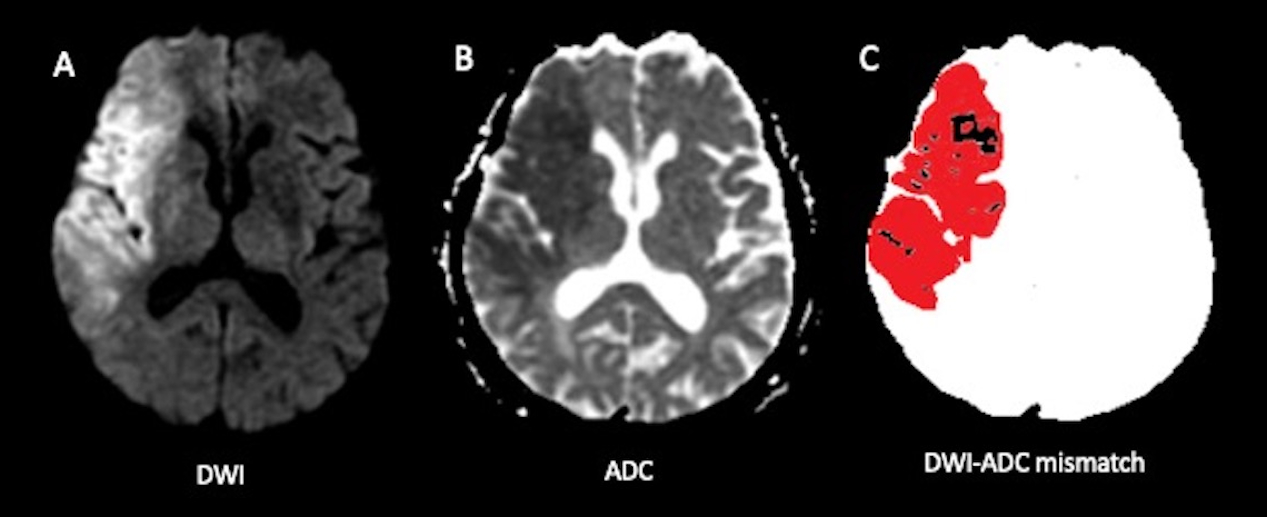

Introduction: An apparent diffusion coefficient (ADC) threshold of ≤ 620 × 10-6 mm2/s identifies irreversible infarcts and guides endovascular thrombectomy (EVT) decisions. However, in hyperacute ischemic infarcts, diffusion-weighted imaging (DWI) hyperintense lesions can show varying ADC values. This study investigates DWI-ADC mismatch, defined as the significant difference between DWI hyperintense lesion volume and ADC ≤ 620 × 10-6 mm2/s volume.

Methods: This retrospective, single-center study included patients with acute large vessel occlusion in the anterior circulation who: (1) underwent MRI within 24 hours of stroke onset, (2) received EVT, and (3) had follow-up MRI within 5 days of EVT from January 2018 to January 2020. Neuroradiologists segmented DWI hyperintense infarcts with ADC hypointensity on pre- and post-EVT MRI, using Fluid-attenuated inversion recovery (FLAIR) sequences to avoid T2 shine-through effects. The DWI/ADC volume ratio was calculated by dividing DWI volume by ADC ≤ 620 × 10-6 mm2/s volume. DWI-ADC mismatch was defined as a DWI/ADC ratio ≥ 2, with no mismatch indicated by a ratio < 2. Final infarct segmentation included hemorrhagic transformation. DWI lesion reversal (DWIR) was defined as the volume of normal-appearing voxels on follow-up DWI but previously hyperintense. DWIR% = (DWIR/baseline DWI volume) × 100 was calculated. We compared demographics, radiological findings, clinical outcomes, and follow-up results between mismatch and no mismatch groups.